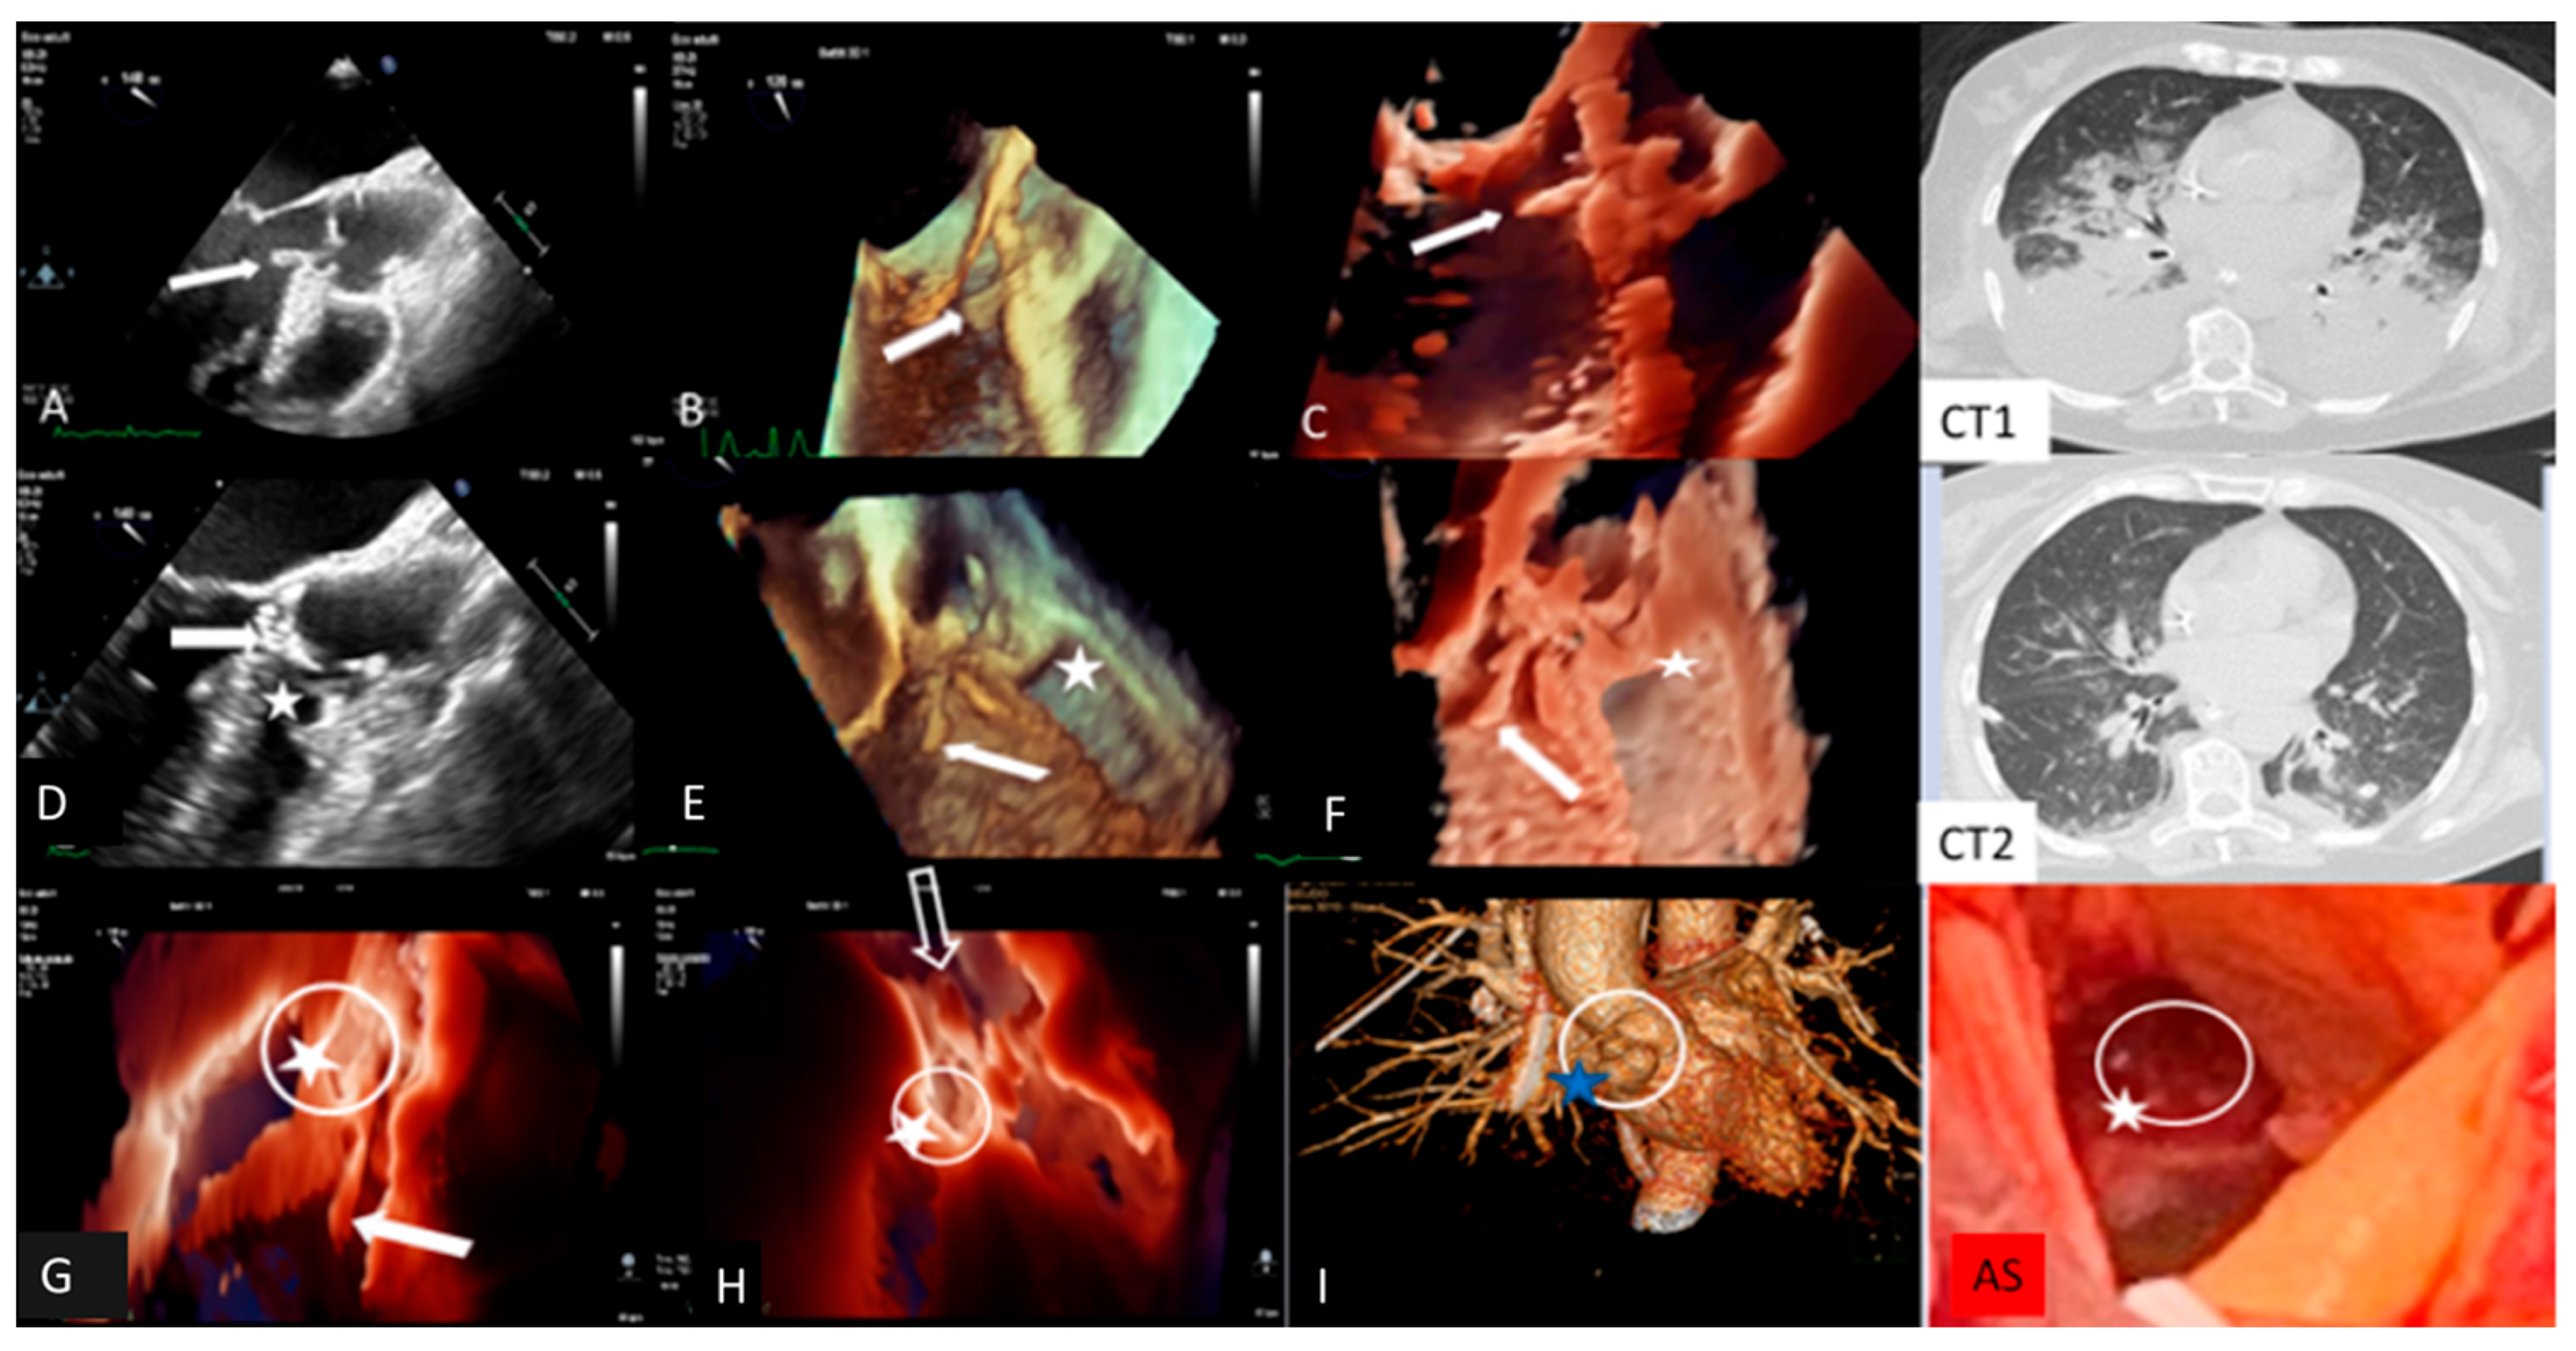

Clinical Case 5. Streptococcus pneumoniae infection with meningitis, pneumonia, and fulminant endocarditis (“Austrian syndrome”). A 72-year-old female was admitted after 3 days of fever, shortness of breath, and abrupt headache with nausea and vomiting. On admission, the patient appeared confused and troubled. Clinical examination revealed nuchal rigidity without focal neurologic signs. Her temperature was 39 °C, arterial blood pressure 115/60 mm Hg. The clinical diagnosis was initially addressed toward bacterial or viral meningitis vs. COVID-19 with meningoencephalitis phenotype. Lumbar puncture was carried out; cerebrospinal fluid analysis showed hypoglycorrhachia and hyperproteinorrhachia, supporting a diagnosis of probable bacterial meningitis. Empirical antibiotic therapy with intravenous Ceftriaxone, Vancomycin and Dexametasone, was promptly started. A brain CT was negative for intracranial lesions. Baseline and contrast CT showed normal pulmonary findings without parenchymal consolidation or signs of thromboembolism. Pneumococcal antigen in urine was positive and blood culture (BC) showed Gram-positive cocci. Nasopharyngeal Swab (NS) was negative for COVID-19. The final BC result confirms S. pneuomoniae bacteremia, supporting a bacterial meningitis etiology. Targeted antibiotic therapy was introduced, including levofloxacin. After 12 h, the patient showed abrupt cognitive impairment with arterial blood hypotension (80/50 mm Hg) and severe hypoxemia requiring endotracheal intubation. The patient was admitted to the intensive care unit with a diagnosis of pneumococcal meningitis and septic shock. After two days, due to significant clinical improvement, endotracheal intubation was removed. However, during the subsequent two hours the patient showed atrial fibrillation with a high ventricular rate that was reverted with iv amiodarone. Clinical examination revealed a new diastolic regurgitant murmur at cardiac auscultation. Temperature was 37.5°, blood pressure 155/50 mm Hg. Large vegetation with severe AR was shown by TTE. Subsequent TEE confirmed AR due to extensive damage of three valve leaflets with large iso-echogenic (like myocardium echogenicity) vegetation, inserted at the level of the ventricular surface of the right coronary cusps (dimension 20 × 7 mm) and prolapsing in the left ventricular outflow tract. There was moderate MR, pulmonary artery hypertension (sPAP 70 mm Hg), and severe TR. Left ventricular dimension and ejection fraction were normal. A fresh thrombus was found in the left atrial appendage. Inotropic support, with furosemide and heparin infusion, was started. Due to high systemic embolic risk (large aortic valve vegetations and left atrial appendage thrombosis), total body CT was performed. Brain CT was normal, while the thoracic scan revealed bilateral parenchymal consolidation and large pleural effusion with parenchymal edema (Figure 1). Additional NPS and BAL excluded COVID-19. Final diagnosis was “Austrian syndrome” (6), including meningitis, with subsequent pneumoniae and endocarditis due to S. pneumoniae. Although clinically indicated, cardiac surgery was postponed due to the unavailability of an operating room during the COVID-19 outbreak. The next day, hemodynamics remained stable under inotropic, diuretic, and mechanical ventilation support. A new TEE showed unchanged findings, apart from the disappearance of the thrombus in the left atrial appendage. The following day, the patient underwent contrast CT, showing significant improvement of pulmonary findings, a normal coronary anatomy, and double bulging of the aortic root below the coronary artery ostium. Immediate TEE was performed showing, in addition to the previous findings, an intimal tear with a new cavity of the anterior wall of the aortic root at the site of systolic contact of vegetation, suggesting a “kissing” mycotic pseudoaneurysm. In addition, TEE revealed normalization of sPAP and related TR. The patient, due to the added risk of impending root rupture, underwent emergency cardiac surgery. Anatomical inspection confirmed large vegetation and extensive leaflet damage of the tricuspid aortic valve, with a large paravalvular mycotic pseudoaneurysm (Figure 1). The operating strategy involved drainage of purulent material and pseudoaneurysm patch repair, followed by biological valve prosthesis implantation. The leaflet aortic culture was positive for S. Pneumoniae. The postoperative clinical course was uneventful, with complete recovery of the clinical condition. Comment. This case outlines the importance of careful daily clinical examination to target the appropriate pathway for the identification and management of unexpected fulminant IE, which can be superimposed in the deceptive context of meningitis and pneumonia due to S. pneumoniae infection (so-called Austrian syndrome).

![]() |

| Transesophageal echocardiography and computed tomography of fulminant aortic endocarditis. TEE images: (A) two-dimensional; (B) three-dimensional; (C): photorealistic three-dimensional showing large vegetation (arrow) on the aortic valve prolapsing during diastole into LVOT, increasing at 24 h TEE images (D–F) together with an intimal tear communicating with a neocavity (star) on the aortic anterior wall at the site of vegetation contact (dotted arrow), suggesting a mycotic pseudoaneurysm; (I): three-dimensional computed tomography showing double bulging of the anterior aortic wall (dotted circle) overlapping photorealistic 3D images (G,H) and surgical specimen findings (AS). Computed tomography showing bilateral pulmonary parenchymal consolidation and large pleural effusion (CT1), which improved following thoracentesis and intensive medical therapy (CT2). |